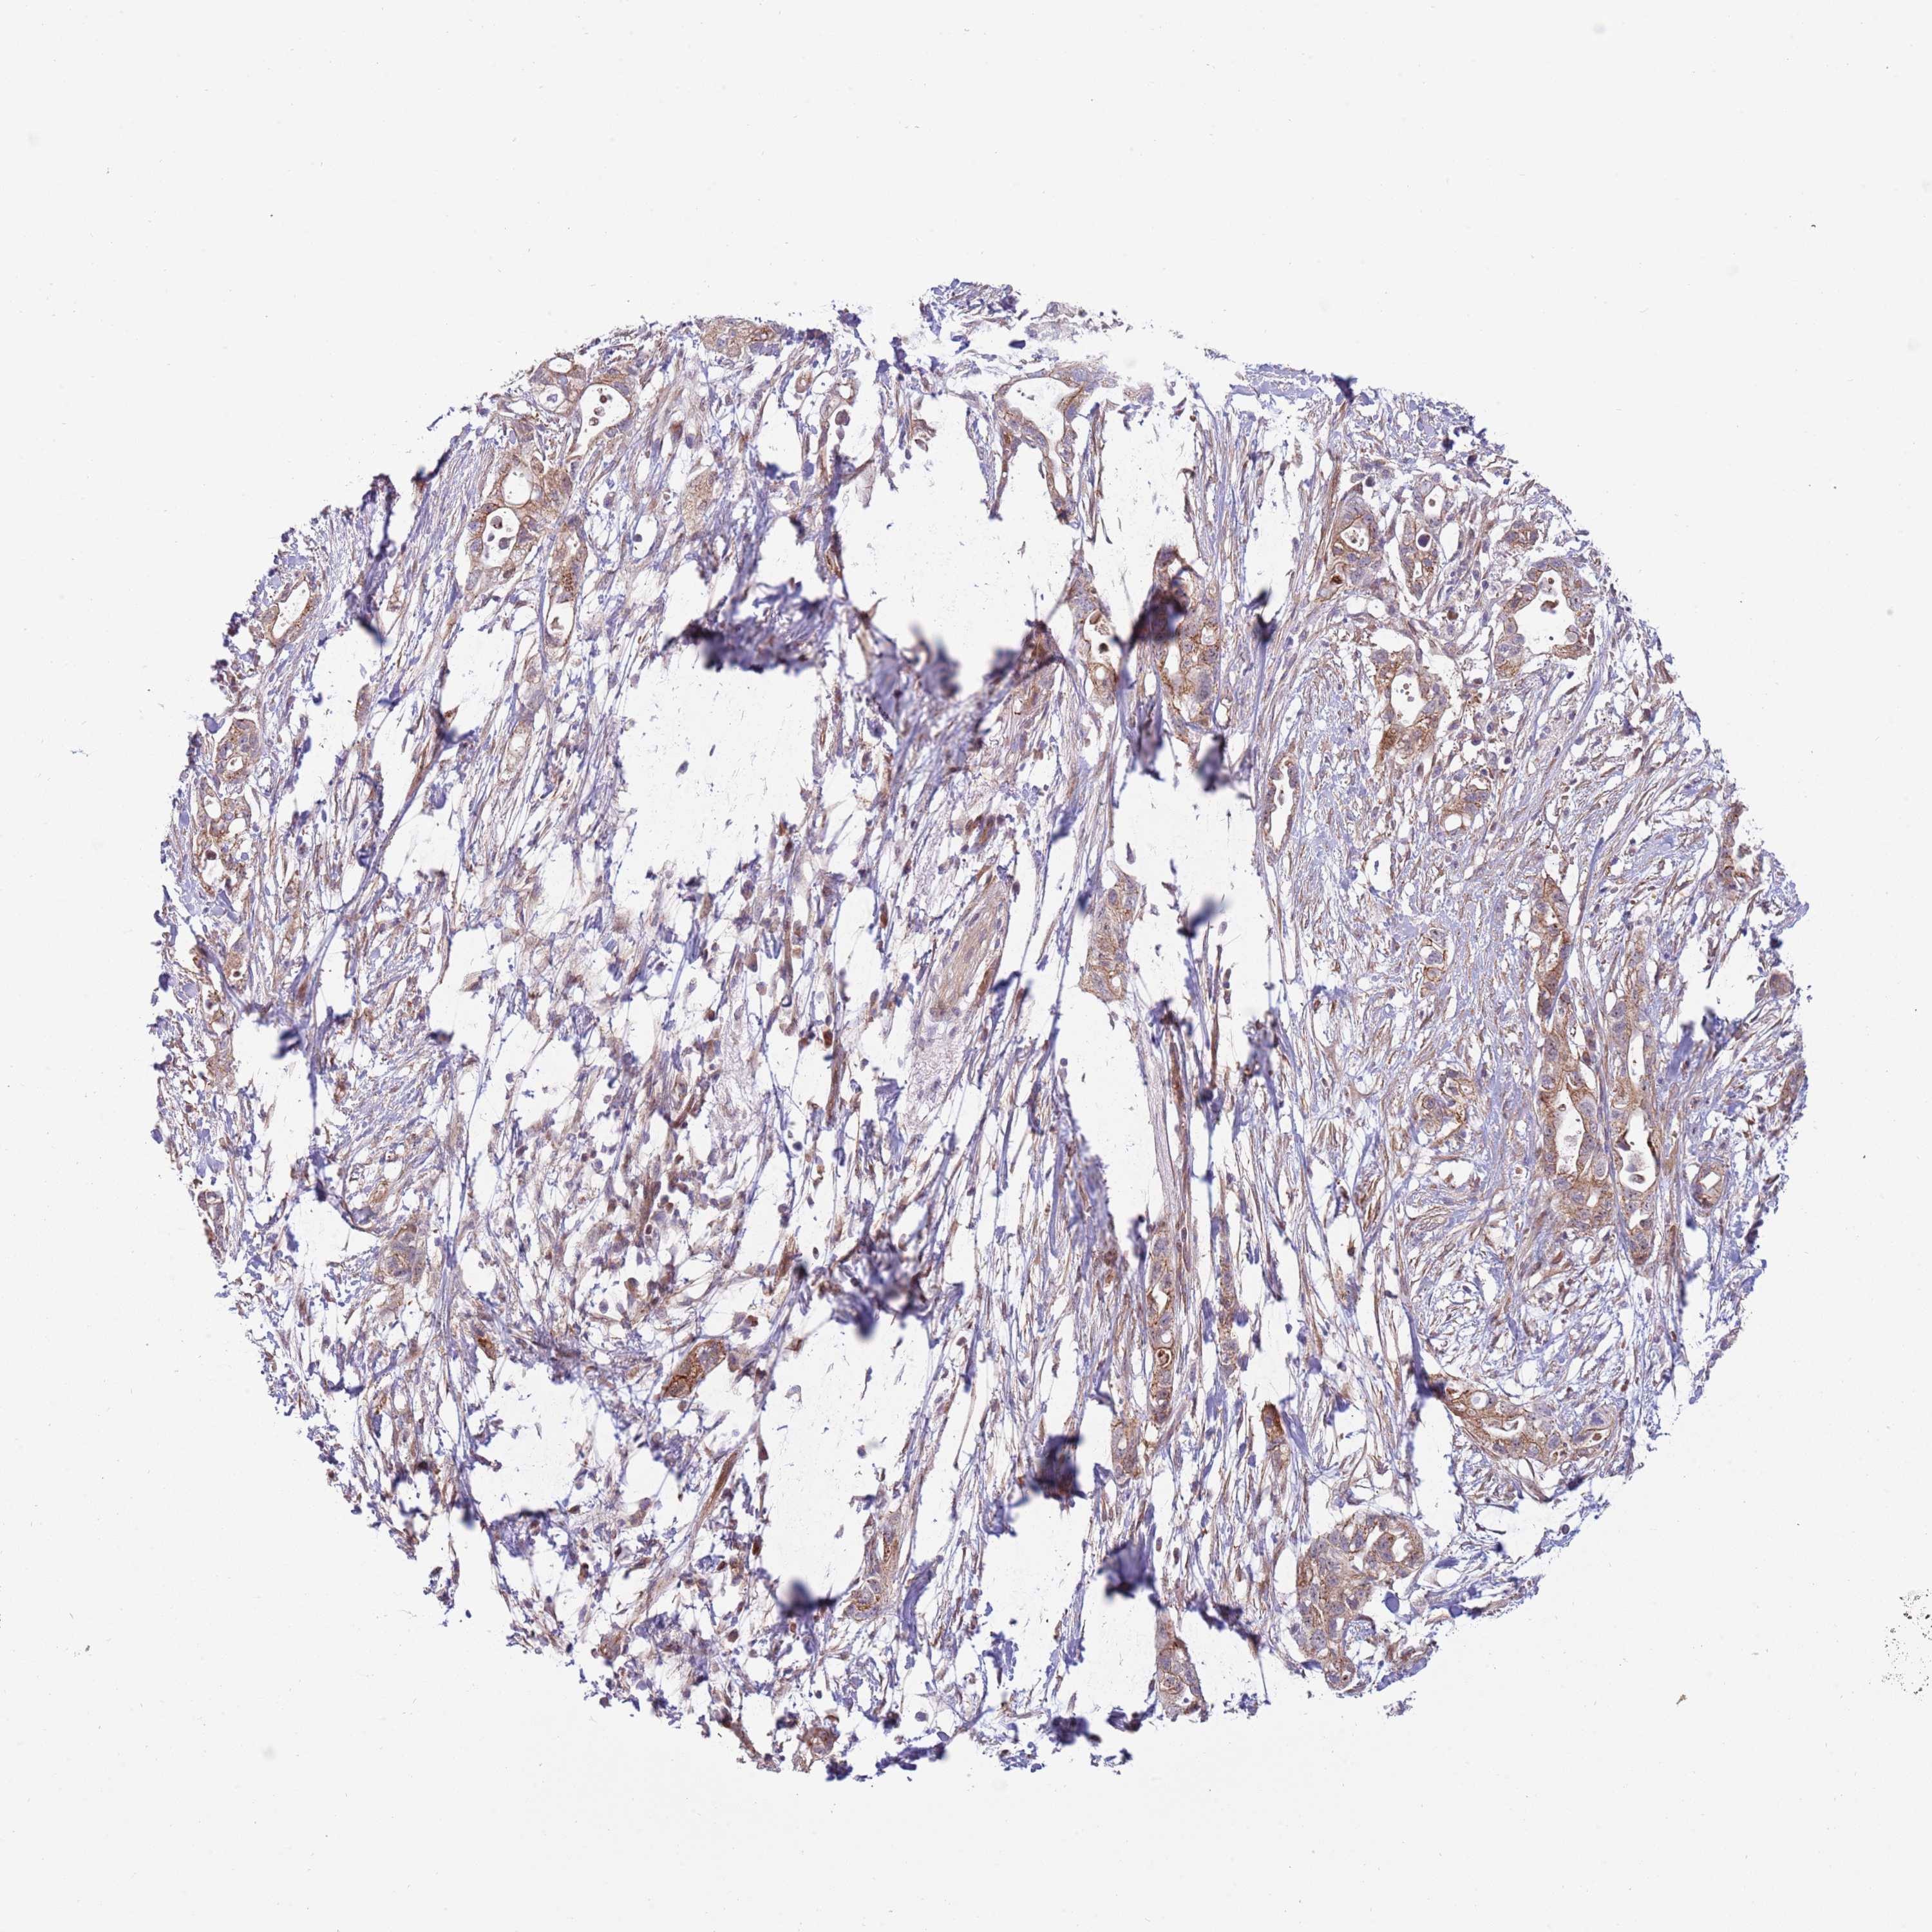

PANCREATIC CANCER - Protein expressioni

A mouse-over function shows sample information and annotation data. Click on an image to view it in a full screen mode. Samples can be filtered based on level of antibody staining by selecting one or several of the following categories: high, medium, low and not detected. The assay and annotation is described here.

Note that samples used for immunohistochemistry by the Human Protein Atlas do not correspond to samples in the TCGA dataset.

Antibody stainingi

Antibody staining in the annotated cell types in the current human tissue is reported as not detected, low, medium, or high, based on conventional immunohistochemistry profiling in selected tissues. This score is based on the combination of the staining intensity and fraction of stained cells.

Each image is clickable and will lead to virtual microscopy that enables deeper exploration of all samples and also displays staining intensity scores, fraction scores and subcellular localization as well as patient and tissue information for each sample.

Antibody HPA023626

Antibody CAB073536

Staining

High

Medium

Low

Not detected

Intensity

Strong

Moderate

Weak

Negative

Quantity

>75%

75%-25%

<25%

None

Location

Nuclear

Cytoplasmic/membranous

Cytoplasmic/membranous,nuclear

Adenocarcinoma, NOS